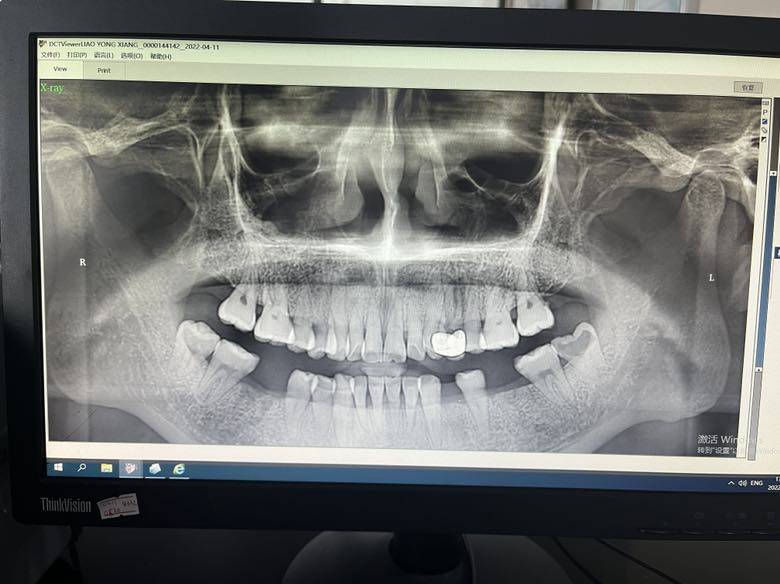

不知道是不是吃多年激素的原因,牙齿一年不如一年。目前已经拔了三颗牙齿了,一颗做了根管治疗,还有一颗已经坏了,待拔。还有一颗断了一半,估计也保留不了多久了。而且,牙齿楔状缺损,龋病。哎呀,才三十几岁的人而已啊,却已经是老年人的牙齿状态了。。从小比较注意口腔卫生,也是正确刷牙方式。但是……哎,悲哀!病友们有牙齿方面的烦恼吗

辛勤的胡萝卜我的牙齿都是从根部断了,已经坏了70%了,都是激素害的,骨质疏松

我18年前后一直为牙齿忙活,嘴里几乎都补过。还有一个假牙,两个根管治疗。后来冲牙器,早晚刷牙,午休有条件也刷牙,买了电动牙刷,牙线,一定要清洁到位。维持现状就是最好的控制